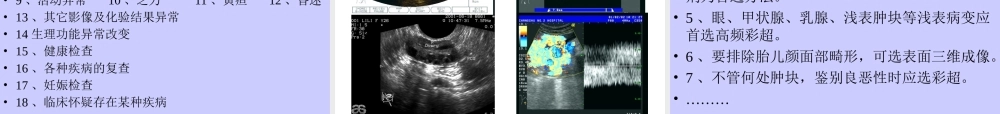

超声的临床应用徐伟忠  超声的分类• 1 、 A 超 : 目前仅用于眼轴的测量。• 2 、 B 超:可用于全身组织器官的检查。• 3 、彩超:有多种模式,用于心脏、血管的检查,液 - 实性病变的鉴别。• 4 、三维超声:(血管,表面,实体)。• 5 、介入超声:腔内检查(直肠、阴道、血管、食道等)及超声引导下穿刺,进行诊断和治疗。 一、常规二维超声成像应用 分类 1. 低频超声 (2.0-2.5MHz) 用于肥胖病人及成人颅脑检查。有时亦用于体躯宽大及肥胖者心脏检查。 2. 中频超声 (3.0-4.0MHz) 用于一般病人腹部脏器、泌尿科、妇产科、腹腔、盆腔等脏器检查。 3. 高频超声 (5.0-10MHz) 用于眼球、颈部血管、甲状腺、乳房、睾丸等浅部小器官检查。 低频超声(心脏)• 肥厚性心肌病,法四 中频超声(腹部脏器)• 重度肾积水,胡桃荚征 高频超声(小器官、浅表组织)• 乳腺纤维瘤,血管病变 二、彩色血流成像应用: 分类: 1. 超声彩色多普勒血流成像 (CDFI) 红细胞流动时散射的频移信息作彩色编码后成像。较常用。管壁、心壁及心瓣膜的低频信息一般均予滤去。用作血流动力学诊断。 2. 超声彩色流速成像 (CVI) 非多普勒效应血流成像,对 θ 角的角度依赖效应降至最低,并消除了混叠伪差。 3. 超声彩色多普勒能量图(CDE) 为多普勒频移信息中的能量(即与振幅平方有关)的血流成像技术 , 灵敏度高。 超声彩色多普勒组织成像 (DTI) 心壁、瓣膜、血管壁活动时的多普勒频移信号接收后彩色编码成像,而将血流的高频 ( 低振幅 ) 信息滤去。用于显示心壁收缩的异常改变。 分析原则(一)超声彩色多普勒血流成像及超声彩色流速成像 1 . 观察、测量血流流速(合理调节灵敏度) 2 . 分析血流方向。 3 . 分析流层改变。正常血管的流层无交叉混杂。(二)彩色多普勒组织成像 1 . 血流被低通滤波器滤去 , 无任何彩色。 2 . 组织活动所产生的多普勒信号显示为彩色。 3 . 可发现活动组织内的静止组织,或者活动组织中活动特别大的部分。(三)超声彩色多普勒能量图 1 . 灵敏度高。 2 . 动、静脉同一色彩,混合成像。 3 . 用于显示血管树的整体分布。 4 . 成像速度缓慢、脏器慢速运动可产生大量闪彩干扰。 5 . 新型方向性能量图。 ( 四 ) 超声彩色血流成像 ( 除 DTI 外 ) 在疾病分析中的规律 层流、射流、湍流、涡流、分流。 应用范围 :...